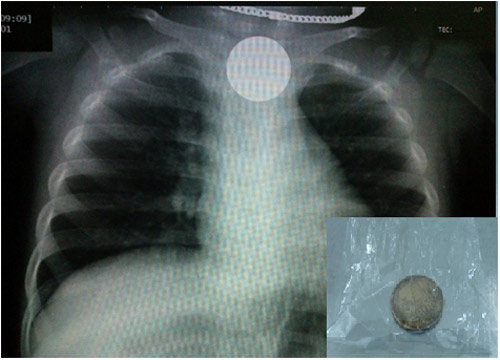

Bệnh nhi là bé N.Đ.H, ở Quận 7, TP.HCM, nhập viện trong tình trạng nôn nhiều có kèm theo ho. Sau khi xem kết quả chụp X-quang ngực, bác sĩ phát hiện trong thực quản đoạn cao của trẻ có dị vật cản quang hình tròn.

Kết quả chụp X-quang và đồng xu sau khi được gắp ra khỏi thực quản của trẻ